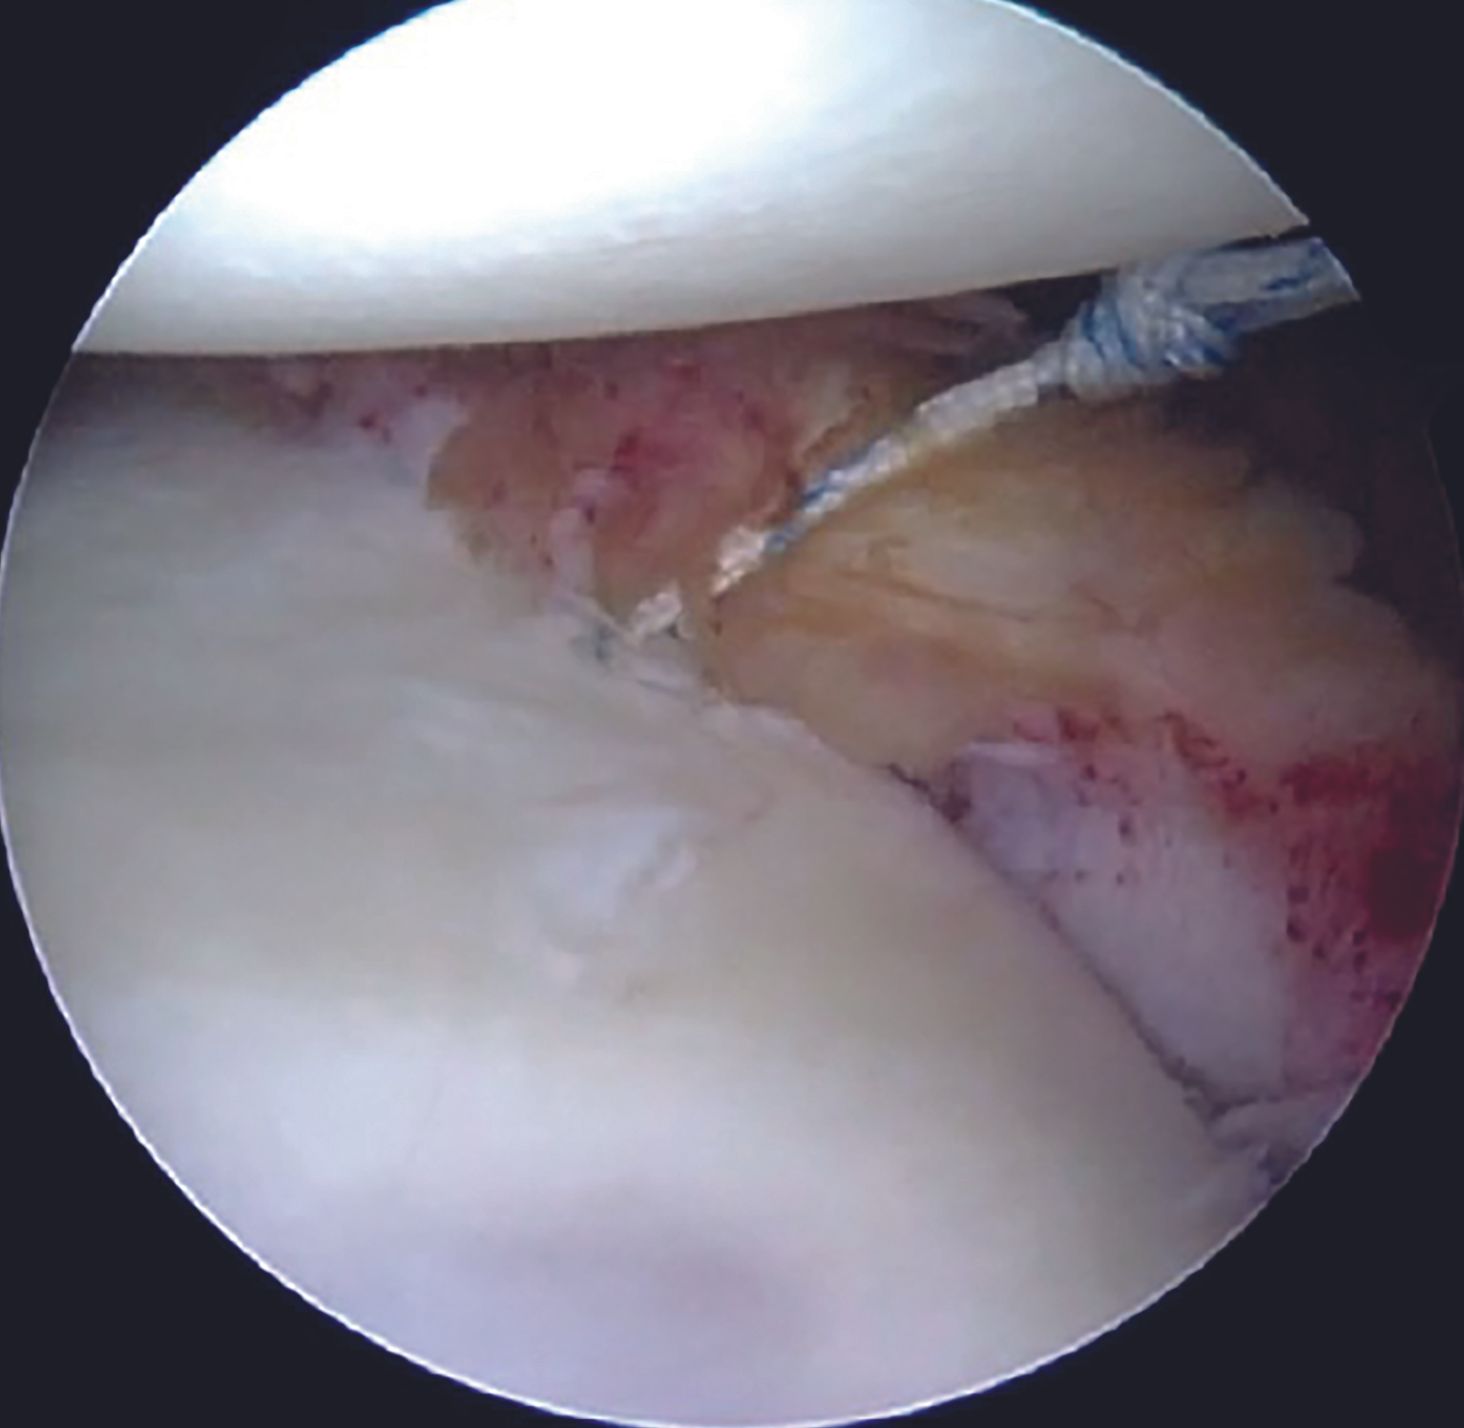

For an isolated Bankart lesion, 3 anchors are usually sufficient. Our preferred choice for the anchor is 1.8mm all-suture anchor as the affected patients are young and thus possess a good quality of the subchondral bone. Advantages of all-suture anchors such as absence of metal implants, no interference with post-operative imaging, easier revision, are well known. Anchor with a tape is preferable to avoid cut-through through the labral tissue. Inferior most anchor is placed first at 5-5.30 O'clock position after drilling a hole using a sleeve through the AI portal (Figure 9). After tapping the anchor in, it is important to pull the tapes so that the anchor bunches up beneath the subchondral bone (Figure 10). Free passage of the tapes is ensured.

Shuttling the tapes and knot tying

One of the tapes is then retrieved through the posterior portal with a tape retriever (Figure 11) and then shuttled through the labral tissue using a suture passer device (Figure 12,13).